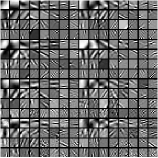

Fig.Β 3 presents an example of the pixel-level clustering in the central axial slice achieved with the PWLS-ULTRA method for . Since PWLS-ULTRA clusters patches, we cluster individual pixels using a majority vote among the 3D patches that overlap the pixel. Class contains most of the soft tissues; class comprises most of the bones and blood vessels; classes and have some high-contrast edges oriented along specific directions; and class mainly includes low-contrast edges. Since the clustering step (during both training and reconstruction) is unsupervised, i.e., different anatomical structures were not labeled manually, there are also a few edges with high pixel intensities included in class . The trained (3D) transforms (with ) for each cluster are also displayed in a similar manner as in Fig.Β 1. The transforms show features (e.g., with specific orientations) that clearly reflect the properties of the patches/tissues in each class.